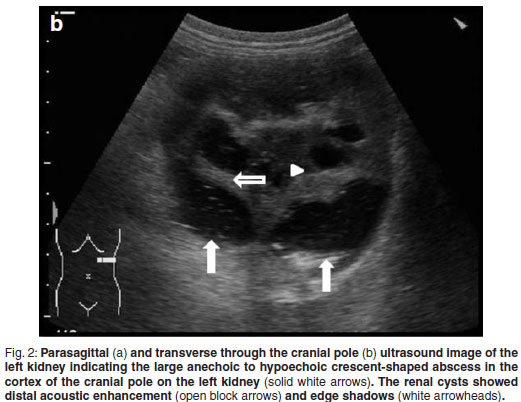

A 5-year-old, fawn, fully vaccinated, intact, male Boerboel weighing 58 kg was presented to the Onderstepoort Veterinary Academic Hospital (OVAH). The history suggested a change in the sexual behaviour of the dog with an increased tendency to 'mount' other dogs. Red discoloration of the urine for 2 weeks before presentation was noted. The only abnormalities that were seen on clinical examination were areas of echymoses on the penile mucosa. Faecal analysis was normal. Urine was collected via cystocentesis and analysed with the following findings: urine specific gravity (SG) 1.018, pH 7, proteins 1+, blood/haemoglobin 3+, erythrocytes 2+ and reticuloendothelial cells 1+. Abdominal ultrasound was performed using a Siemens Sonoline Omnia (Siemens AG, Erlangen, Germany) ultrasound machine and a mutli-frequency curvilinear array transducer operated at 5 MHz. This revealed multiple bilateral cystic structures measuring up to 13 mm in the medulla of the kidneys (Fig. 1). The prostate was normal in size with patchy hypo-to anechoic mottled areas. Bilaterally on the cranio-lateral aspect of the prostate there were more anechoic focal fluid accumulations up to 20 mm in diameter. The cytology of the ultrasoundguided fine-needle aspirates (FNA) was consistent with benign prostatic hyperplasia. Owing to financial constraints the owners declined further diagnostics and blood tests. The dog was castrated by the referring veterinarian.

Abdominal ultrasonography was performed under sedation using medetomidine (Domitor, Pfizer, 1 mg/kg) at a dose of 10 µg/kg intravenously. The left kidney measured 10×6×7.5 cm with a slightly uneven margin (cranial pole was larger). A small amount of hypoechoic subcapsular fluid surrounded the kidney. Multiple round, well-marginated, anechoic, cystic structures were seen mainly in the medulla with some extending into the cortex. The largest of these measured 2.5 × 1.5 × 2 cm. These cysts had a clear edge shadow, distal acoustic enhancement with a thin but clear hyperechoic far wall (Fig. 2a,b). Some cysts contained multiple internal hyperechoic specks. The renal cortex was normoechoic and the corticomedullary junction was distinct. Two of the cranial pole cysts of the kidney were more hypoechoic and communicated with a large 5×3×3cm hypoechoic well-marginated, crescentshaped mass which distorted the cranial pole of the kidney. This structure had hyperechoic septa and multiple hyperechoic internal specks that swirled on ballotment. Acoustic enhancement and edge shadowing were seen. Slice thickness artefact was noted in the mass mimicking sediment. No gas was noted in the mass. The right kidney measured 11 × 6 × 5 cm. Multiple smaller (largest about 1×1×1.5 cm) anechoic structures were present mainly in the medulla (Fig. 3a,b). Some of these cysts communicated with each other and some had multiple hyperechoic internal specks. No cysts were found in any of the other abdominal organs, including the pancreas and the liver. The ultrasonographic diagnosis was atypical multiple renal cysts with a suspected large left renal cranial pole cortical abscess. Other individual complicated cysts could not be excluded. The differential diagnosis for cyst-like structures included uniform blood clots, unclotted blood, abscesses without debris, lymphomatous masses and necrosis related to tumours or cystadenocarcinomas35.